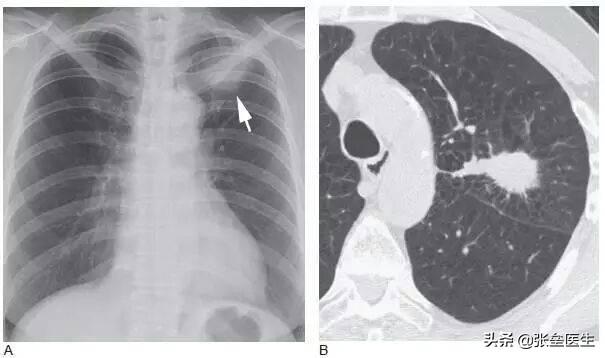

これはまだクリニックでは比較的よくあることで、旅行で広州に来た患者さんが突然咳や痰が再発し、当院を受診したところ、左下肺に結節性病変があり、いくつかの影が確認できたということがありました。その時、北方から来たこの患者さんは1ヶ月前に地元のある病院を受診し、急性気管支炎で抗生物質と痰を取る薬で一定期間治療を受けており、旅行で広州に来る予定だったのですが、思いがけず到着後数日で症状が再発し、最終的に非小細胞がんと診断されました。その結果、到着後わずか数日で咳と痰の症状が再び現れるとは思ってもみなかったようで、最終的に非小細胞がんと診断された。実際、この患者を診断するのは容易ではなく、CT、喀痰培養などいくつかの検査を経て初めてがん細胞が見つかり、初期症状も明らかではなかった。従って、咳や痰は肺癌の初期症状とも言えるが、実際には咳や痰の原因があまりにも多く、しかも頻度が高いために軽視されやすいことは誰もが認めるところである!

しかし、どのような形で症状が現れたとしても、初期の肺がんを発見する最善の方法は、肺がん検診を受けるには低線量スパイラルCT検査を受けることだと、私たち医師は今でも強調しています。臨床症状は肺がんの発病に遅れることが多い症状から肺がんを早期発見するためには、末期になる確率が高く、特に肺がんのリスクが高い人は、健康診断に注意することが大切です!

低線量胸部CTは早期肺癌を発見する最も有効な方法であり、早期末梢肺癌を早期に発見することができる。